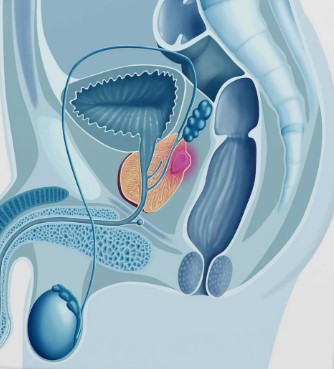

Prostata (neboli mužská prostata) se nachází pod spodní částí močového měchýře mezi stydkou kostí a konečníkem. Prostatická část močové trubice prochází tkání prostaty. U dospělého muže je hmotnost prostaty 15-28 gramů; u dětí je velikost prostaty velmi malá.

Vzhledem k obrovskému vlivu prostaty na fungování pohlavního systému a celého mužského těla se o ní často hovoří jako o druhém srdci muže.

Příznaky rakoviny prostaty se v raných stadiích obvykle neprojevují. Kromě adenokarcinomu mají lidé se zvýšeným rizikem vzniku karcinomu prostaty téměř vždy souběžné patologické stavy (zánět prostaty, adenom prostaty) a ty mohou vyvolat příznaky.

Existují dvě skupiny příčin problémů s prostatou: infekce a přetížení. Infekční prostatitida může být způsobena různými bakteriemi, viry nebo plísněmi. Nejčastějšími původci jsou nespecifické mikroorganismy: stafylokoky, streptokoky, Escherichia coli, Proteus, o něco méně často specifické mikroorganismy: gonokoky, trichomonády a další. V poslední době se zvyšuje počet chlamydiových, mykoplazmových aj. prostatitid.